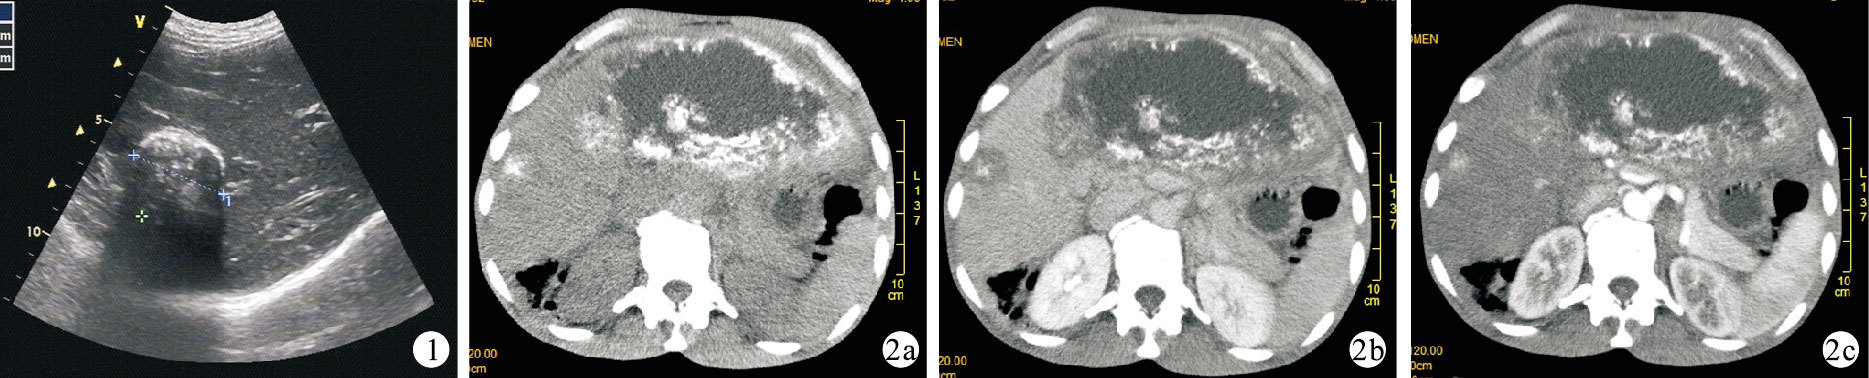

51例患者CT及彩色多普勒超聲均發現肝臟占位病灶,檢出率100.0%,其中彩色多普勒超聲診斷肝包蟲病37例,陽性率72.5%;CT診斷肝包蟲病42例,陽性率82.4%。CT及彩色多普勒超聲對肝包蟲病診斷陽性率比較差異無統計學意義(P>0.05)。見表 1。典型患者彩色多普勒超聲及CT圖像見圖 1、2。